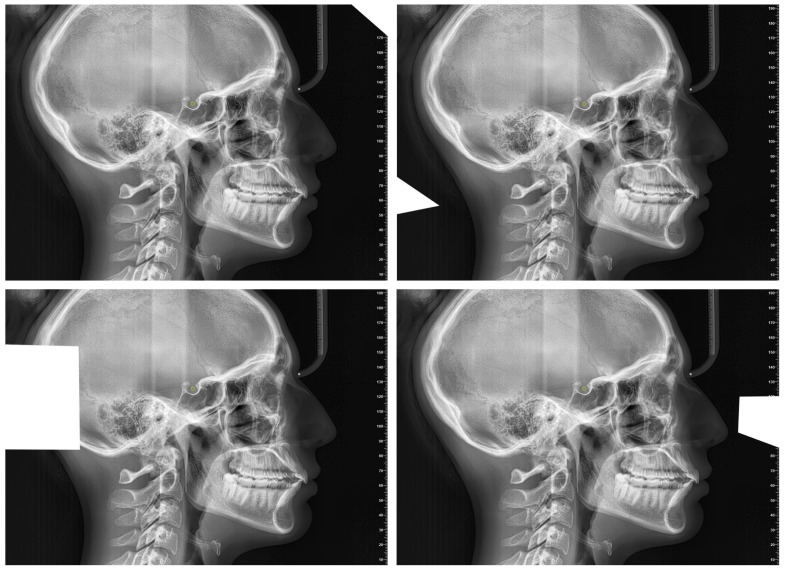

目的:本研究旨在评估人工智能(AI)识别头侧标志的可重复性,并将其与经验丰富的正畸医生手工追踪的性能进行比较。方法:选择一名符合严格入选标准的26岁女性患者的高质量侧位脑电图。使用WebCeph软件(版本1500)在三种实验设置中识别出18个头测地标:不修改图像的人工智能追踪(AInocut)、图像修改的人工智能追踪(AI-cut)和由正畸专家手动追踪。每个评估者在同一幅图像上重复该过程10次。记录X和Y坐标,并使用变异系数(CV)和质心距离分析评估再现性。统计学比较采用单因素方差分析和Bonferroni事后检验,显著性设置为p < 0.05。结果:AInocut重复性最高,平均CV值最低。这两种AI方法都比手动追踪显示出更高的一致性,特别是对于像Menton (Me)和Pogonion (Pog)这样的地标。Gonion (Go)在所有组中表现出最高的变异性。在鼻后棘(PNS)点上发现显著差异(p = 0.001),人工智能优于人工追踪。x轴的变异性一般高于y轴。结论:与经验丰富的操作人员手工追踪相比,人工智能在头测地标识别方面表现出更高的可重复性。虽然某些点表现出很高的一致性,但其他点——尤其是PNS和围棋——仍然具有挑战性。这些发现支持人工智能作为数字头测术的可靠辅助手段,尽管单张x线片的使用限制了其普遍性。需要更广泛的多图像研究来证实其临床适用性。

Objectives: This study aimed to evaluate the reproducibility of artificial intelligence (AI) in identifying cephalometric landmarks, comparing its performance with manual tracing by an experienced orthodontist. Methods: A high-quality lateral cephalogram of a 26-year-old female patient, meeting strict inclusion criteria, was selected. Eighteen cephalometric landmarks were identified using the WebCeph software (version 1500) in three experimental settings: AI tracing without image modification (AInocut), AI tracing with image modification (AI-cut), and manual tracing by an orthodontic expert. Each evaluator repeated the procedure 10 times on the same image. X and Y coordinates were recorded, and reproducibility was assessed using the coefficient of variation (CV) and centroid distance analysis. Statistical comparisons were performed using one-way ANOVA and Bonferroni post hoc tests, with significance set at p < 0.05. Results: AInocut achieved the highest reproducibility, showing the lowest mean CV values. Both AI methods demonstrated greater consistency than manual tracing, particularly for landmarks such as Menton (Me) and Pogonion (Pog). Gonion (Go) showed the highest variability across all groups. Significant differences were found for the Posterior Nasal Spine (PNS) point (p = 0.001), where AI outperformed manual tracing. Variability was generally higher along the X-axis than the Y-axis. Conclusions: AI demonstrated superior reproducibility in cephalometric landmark identification compared to manual tracing by an experienced operator. While certain points showed high consistency, others-particularly PNS and Go-remained challenging. These findings support AI as a reliable adjunct in digital cephalometry, although the use of a single radiograph limits generalizability. Broader, multi-image studies are needed to confirm clinical applicability.